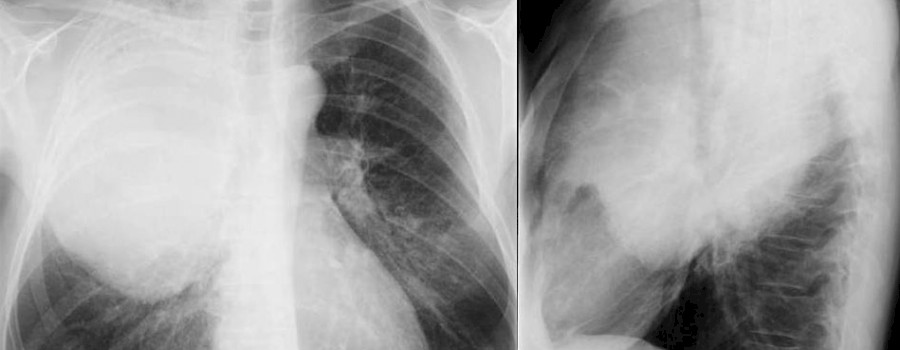

Die Schultereckgelenksverrenkung (auch Schultereckgelenk-Sprengung, AC-Gelenk-Sprengung, ACG-Sprengung oder AC-Sprengung) ist eine durch traumatische äußere Einwirkungen verursachte komplette oder inkomplette Sprengung des Schultereckgelenkes.